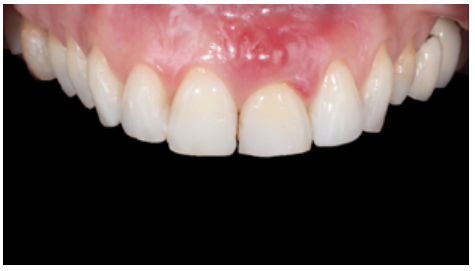

Clinical case: A 32-year-old female patient who attended for a possible root fracture of the upper left central incisor (ULCI), accompanied by a periodontal abscess at the bottom of the vestibule of the same tooth. A clinical and radiological examination established that the prognosis of the ULCI was unfavourable for conservative treatment. After evaluating the clinical features of the case, the treatment plan to extract the ULCI followed immediately by an osseointegrated implant (OII) and loading of a provisional prosthesis on the implant.

Conclusions: Rehabilitation on implants in situations of tooth loss in the aesthetic anterior sector, especially in young patients, requires a multidisciplinary treatment plan to extract the tooth and insert an OII in the correct 3-dimensional position. Various aspects need to be taken into account for this, particularly the residual remaining bone, the position of the gingival margin and preservation and conditioning of the peri-implant hard and soft tissues by means of grafts and proper handling of provisional prosthesis, until an ideal emergence profile and gingival contour is achieved before the final crown.